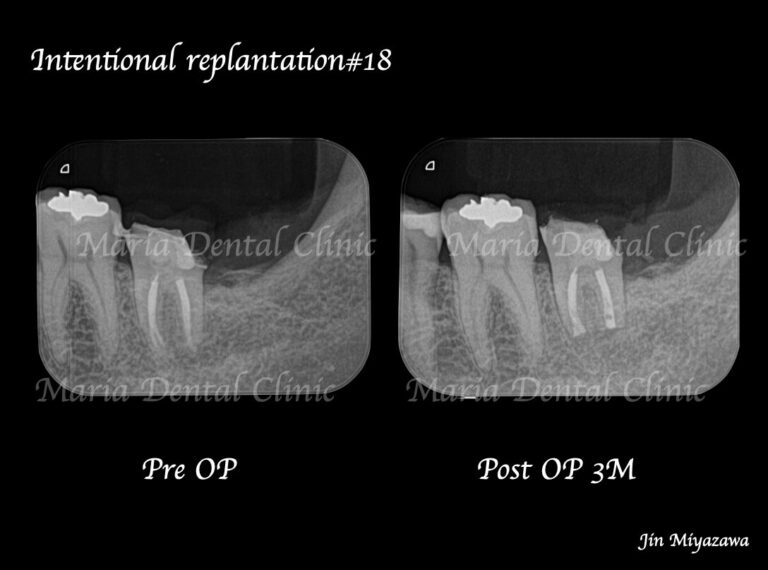

【症例】意図的再植術|歯根破折歯を保存したチャレンジケース